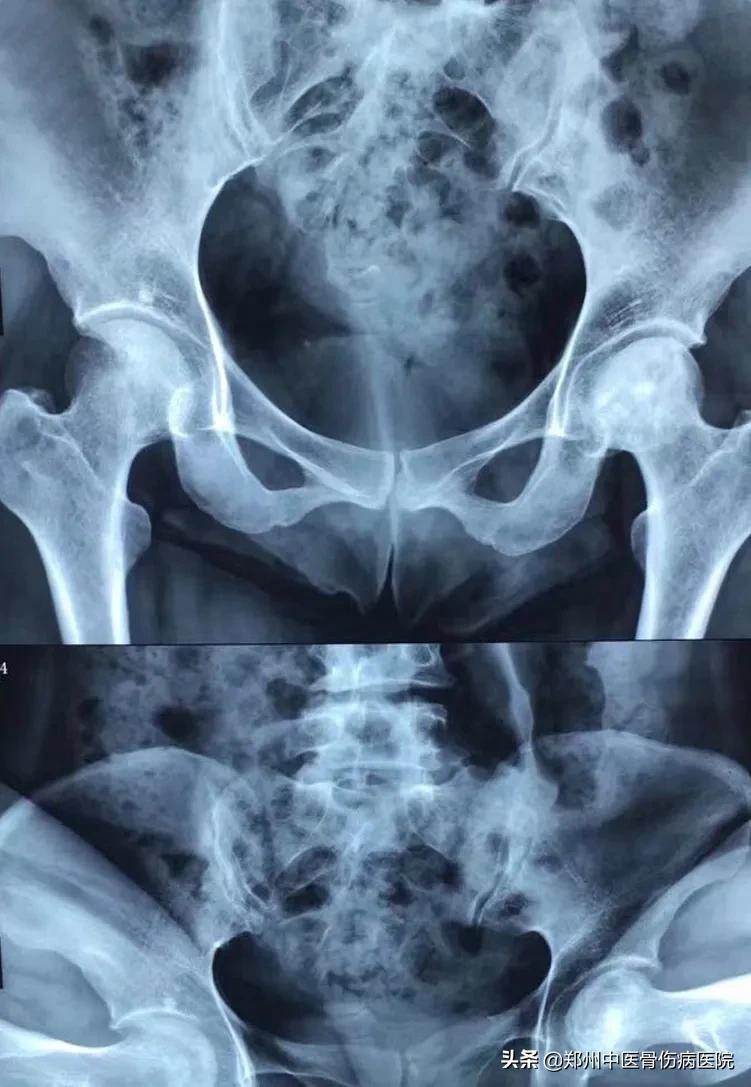

下图为患者康复前后照片对比:头型未再进一步塌陷,骨质密度也越来越均匀

① 患者康复前片子

② 患者康复后片子

入院后,经过相关检查及查体,诊断为双侧股骨头坏死,左侧3期,右侧2期。郭志华大夫详细给患者讲解病情及将来预后情况,并根据我院治疗特色,为患者制定个性化康复方案,住院期间郭大夫经常与病人聊天,疏导心理,患者疼痛症状越来越轻,脸上笑容也渐渐多了起来。

患者经过在我院4次住院治疗,走路由原来的一瘸一拐基本恢复正常,股骨头未再进一步塌陷。根据患者一次次复查情况,药物逐渐减量,现在已经丢掉拐杖,患者生活恢复了正常,一直说,郭大夫,谢谢你,我一定给你送个锦旗。